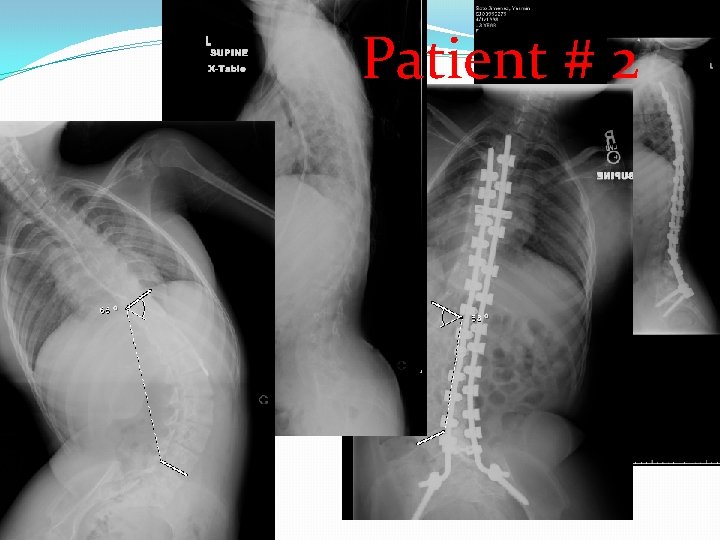

�At the time of surgery, two of these children were over 12 years of age and underwent posterior spinal arthrodesis with segmental spinal instrumentation from T 2 to pelvis. The other patients were under 10 years of age and were treated with spinal instrumentation in a growing rod construct, without arthrodesis. There were no complications from surgery with excellent sagittal and coronal correction of deformity obtained and maintained.

patient age at diagnosis (months) Age at Followsurgery up (months) months surgery Cobb pre-op Cobb post-op sagittal complica tions � #1 96 125 54 ** 54° 18° normal none � #2 96 148 25 *** 66° 53° normal none � #3 96 * 64° � #4 72 117 14 ** 42° 8° normal none � #5 24 154 14 *** 64° 4° normal none * normal • * Pending surgery • ** Segmental spinal instrumentation without arthrodesis • *** Segmental spinal instrumentation with arthrodesis

Patient # 2